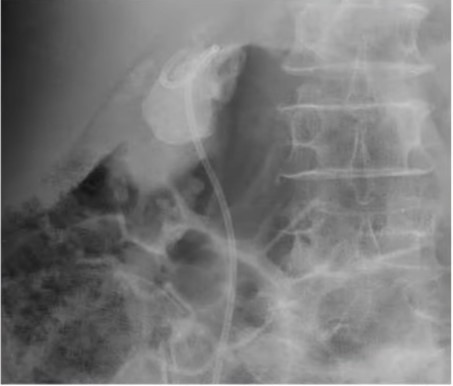

Sỏi san hô xâm lấn các đài bể thận - Ảnh BVCC

Tại phòng khám Ngoại Tiết Niệu Bệnh viện Đa khoa Xuyên Á, người bệnh được thăm khám và chụp CT, xét nghiệm. Kết quả cận lâm sàng ghi nhận bà T. bị sỏi san hô có đường kính 5cm, sỏi từ bể thận bên phải có nhiều nhánh vào đài thận và hầu hết các đài thận còn lại đều có sỏi, gây nhiễm trùng đường tiết niệu.